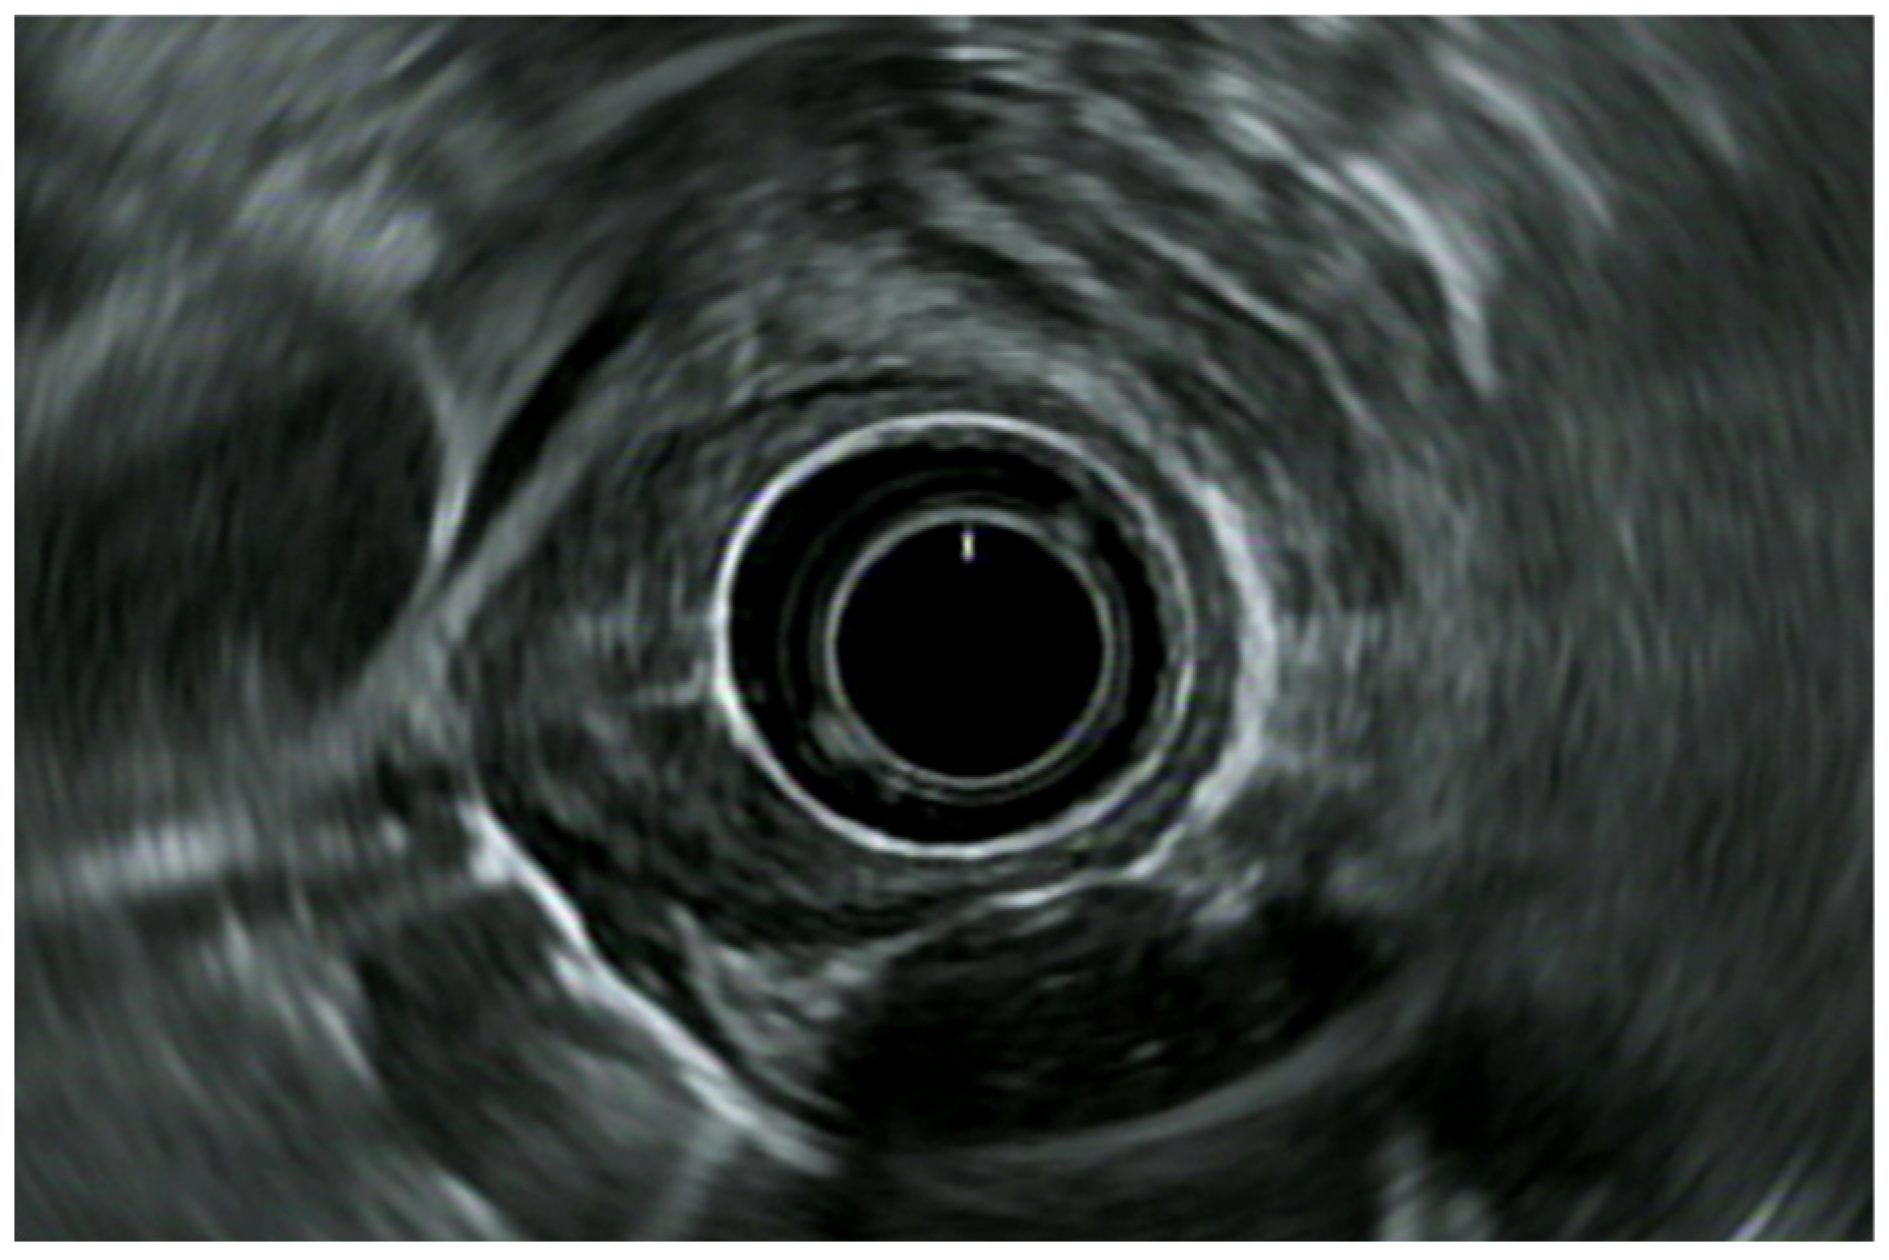

7. Endoscopic Rectal Ultrasound

8. Rectal Neoplastic Lesions